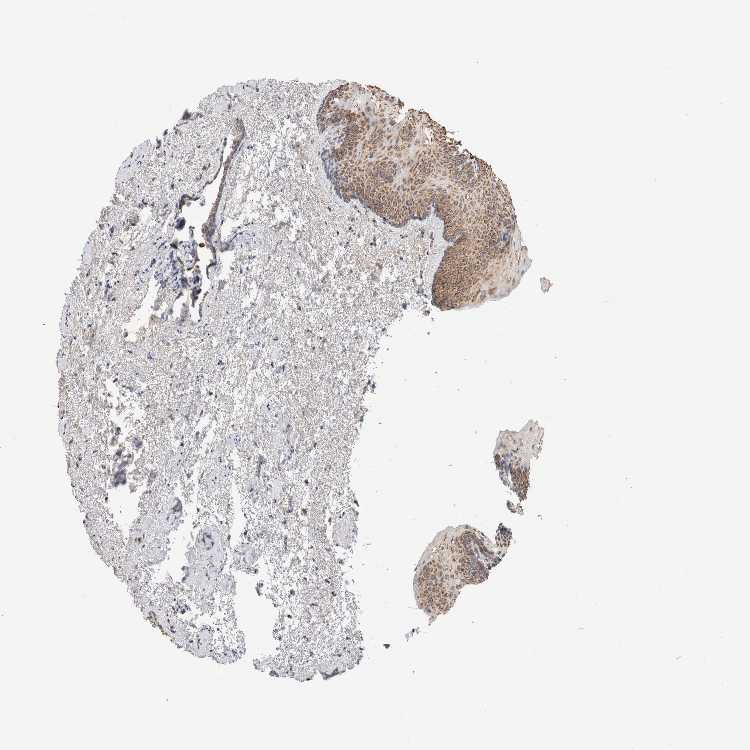

URINARY BLADDER - Antibody stainingi

Antibody staining in the annotated cell types in the current human tissue is reported as not detected, low, medium, or high, based on conventional immunohistochemistry profiling in selected tissues. This score is based on the combination of the staining intensity and fraction of stained cells.

Each image is clickable and will lead to virtual microscopy that enables deeper exploration of all samples and also displays staining intensity scores, fraction scores and subcellular localization as well as patient and tissue information for each sample.

Antibody HPA026483

Urothelial cells Medium